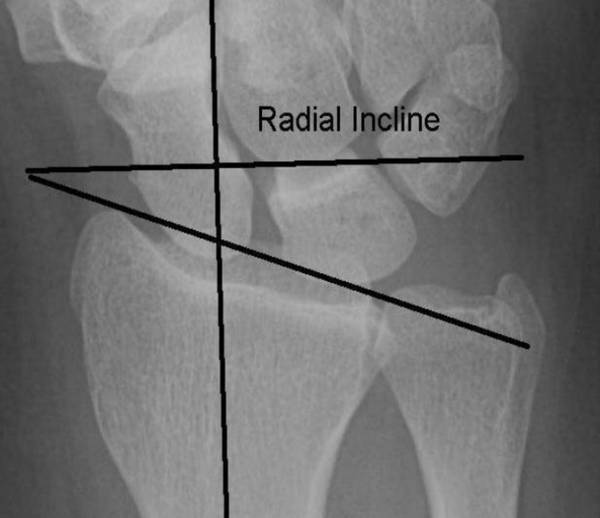

腕关节病人

关节功能评定

陈山林主任的学生刘璐博士在评估腕关节功能